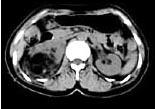

问题 女,53岁,右侧轻度腰背酸痛,行CT检查,如图所示,可能的诊断为 ( )

选项 A、右腹膜后脂肪瘤 B、右肾血管平滑肌脂肪瘤 C、右肾上腺腺瘤 D、右肾上腺嗜铬细胞瘤 E、右肾上腺髓样脂肪瘤

答案 E